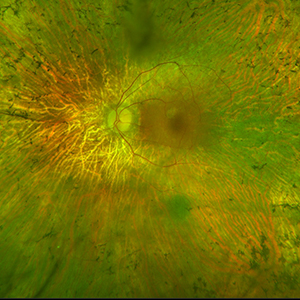

Age-related macular degeneration (AMD)

AMD is one of the commonest causes of visual loss in those older than 50 years of age. Early in the disorder, vision becomes distorted or blurred but in advanced cases, central vision can be lost completely. The decline in central vision makes reading, recognising faces, watching television and driving more difficult. Early signs of AMD include deposits at the macula called drusen. At late stages, AMD can be classified as either dry or wet. In dry AMD, there is progressive loss of cells and thinning at the macula. In wet AMD, bleeding or leakage of fluid in the macula causes rapid loss of vision unless urgent treatment is initiated.

Central serous chorioretinopathy (CSCR)

CSCR is an acute condition where fluid collects underneath the retina and causes a limited retinal detachment. If this involves the macula, the most sensitive part of the retina, it results in blurring of vision. There is a strong association of this condition with steroid use. Although usually self-resolving, sometimes the fluid does not improve and there is a risk of permanent visual impairment. In this situation need treatment mainly by photodynamic therapy which is delivered using a special kind of laser.